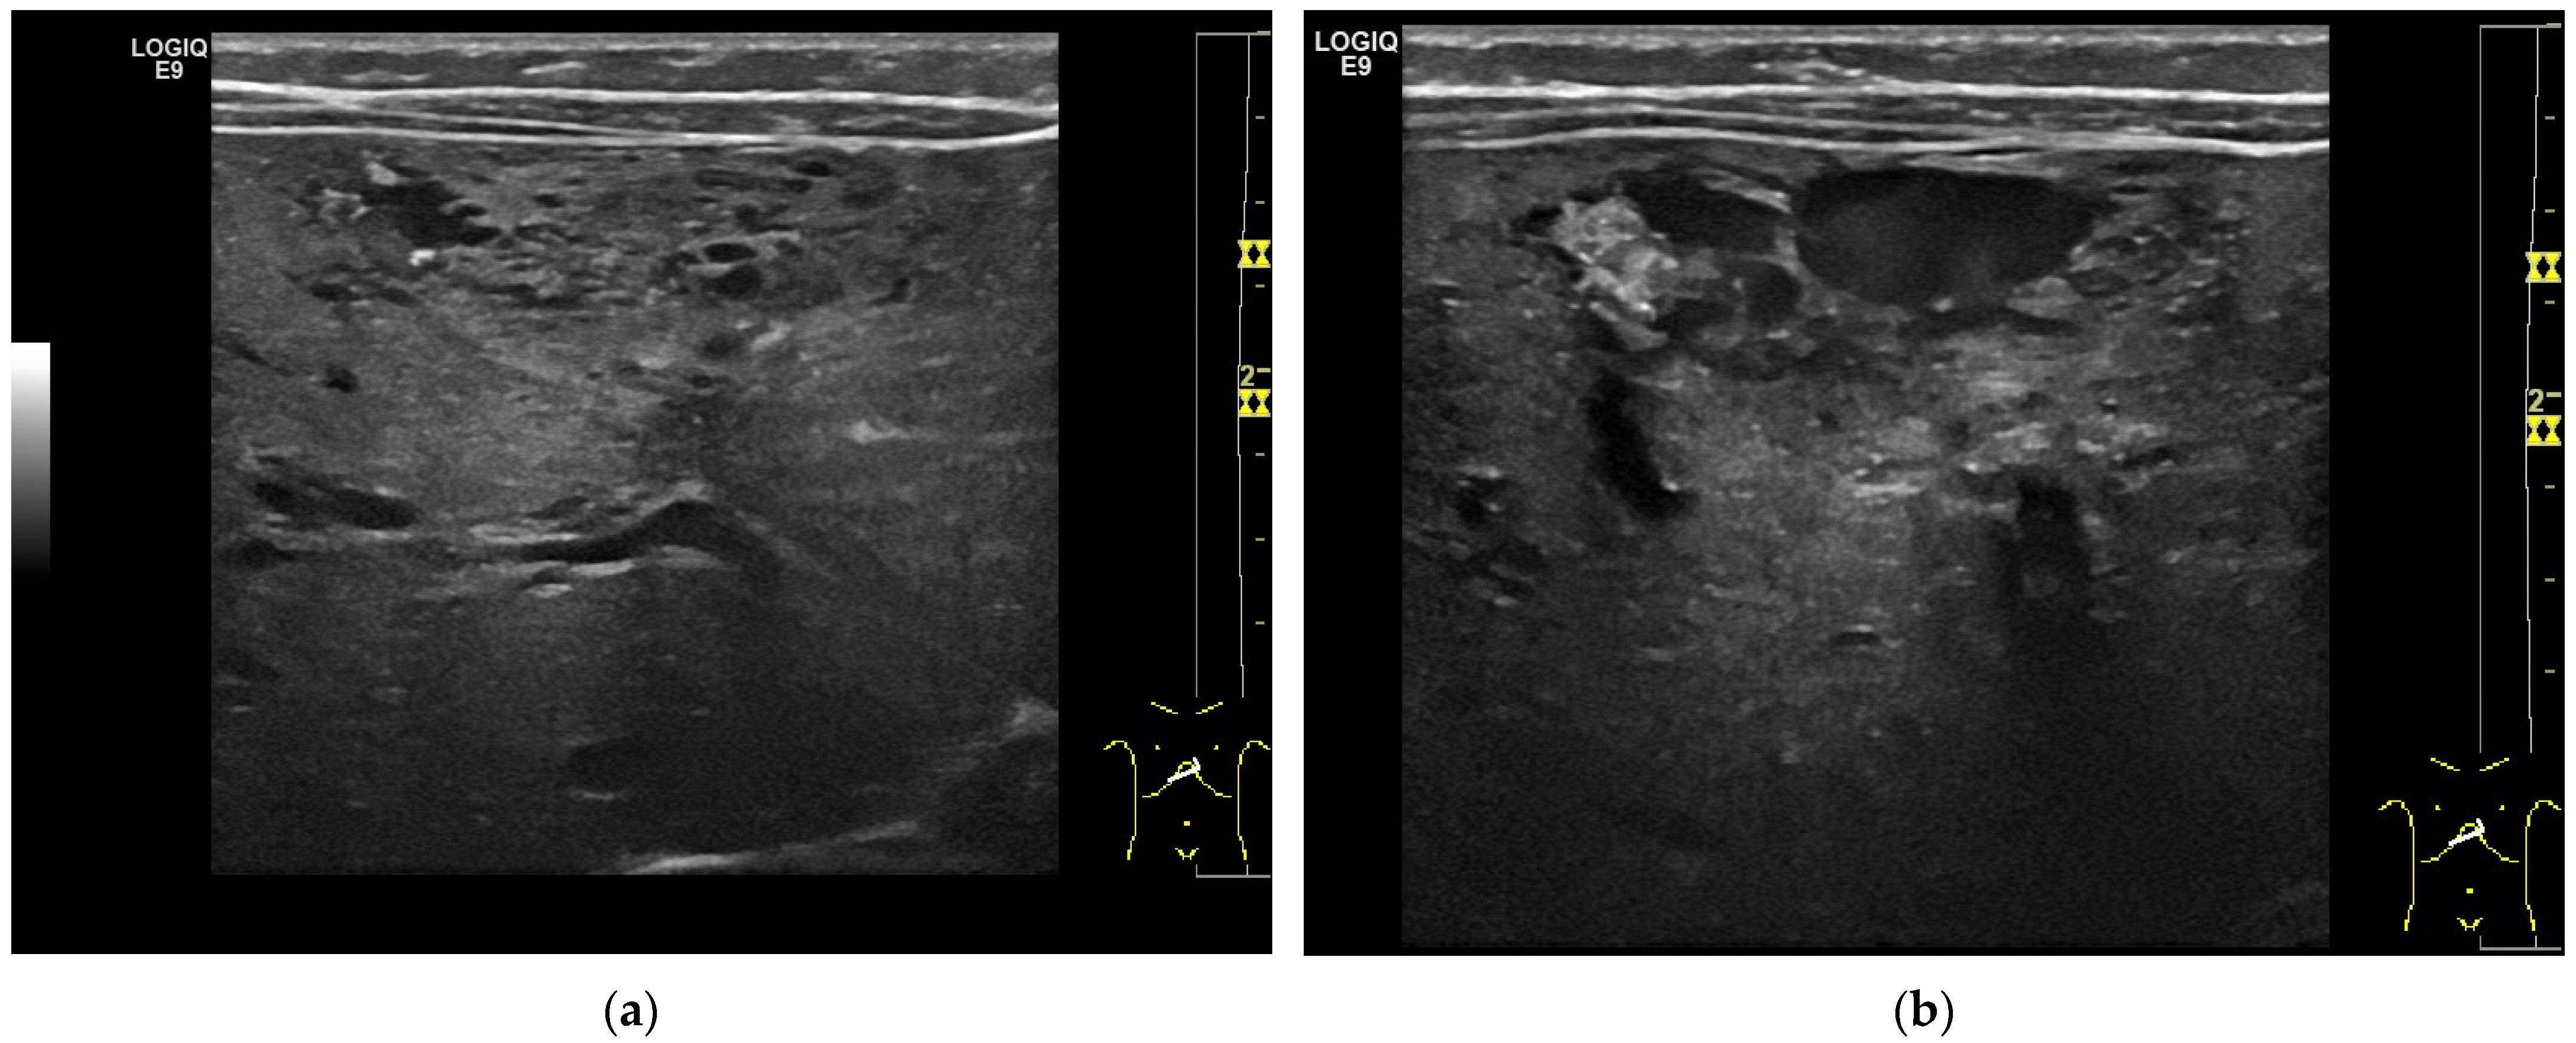

Figure 4.

A 17-year-old female with a focal liver lesion in the right liver lobe and a small oval cyst in the surrounding area (a). Arterial phase hyperenhancement predominantly in the periphery with a rim and septae-like structures with non-enhancing areas (b) and washout are documented (c). Needle biopsy with histological evaluation revealed angiosarcoma of the liver.